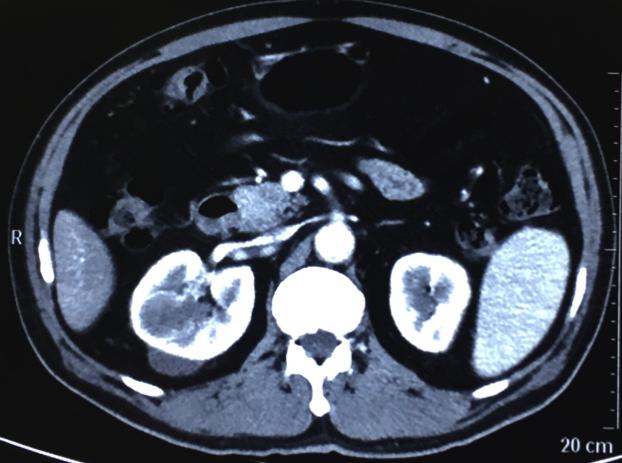

2016.11.23再次复查肾脏CT:右肾MT较前进一步缩小,肝内血管瘤,肝小囊肿同前。

治疗2月缩小到33mm

右肾肿瘤最大径缩短从59mm缩小到33mm,缩小达44%,疗效评价PR。

2016年11月26日行开放性右肾部分切除术,术前停阿昔替尼4天,术中使用B超定位右肾肿瘤,顺利切除右肾肿瘤,保留右肾,术中出血约500ml,未输血。

术后病理:右肾透明细胞肾细胞癌,ISUP分级2级,肿瘤大小:3.5*3*3CM,癌组织坏死(+)。